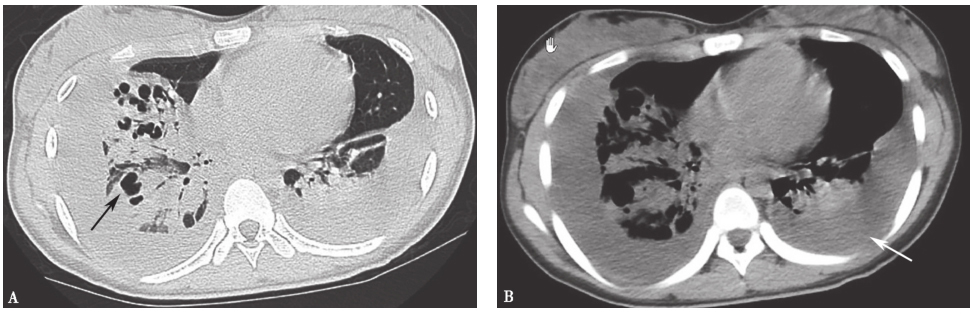

图8 肺脓肿胸部CT表现

女性患者,15岁,发热、咳嗽5天,出现进行性呼吸困难;发病8天后出现多发肺脓肿,伴双侧胸腔积液(佘丹阳教授提供)

图10 腺病毒肺炎影像学表现

男性患者,22岁,发热、咳嗽1周,呼吸困难3天。胸部X线片(A)可见双肺中下肺野为主高密度实变影,双侧肋膈角消失,右侧尤著;胸部CT(B)可见以双下肺为主的弥漫高密度实变影伴支气管充气征,并见双侧胸腔积液。诊断为腺病毒肺炎(贺蓓教授供稿)